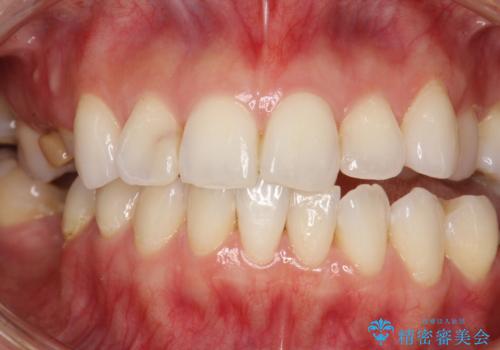

PMTC30分コース(保険外治療)を行いました。かなり久しぶりの歯科医院へ来院とのことで、プラーク(歯垢)・歯石・ステイン(着色)が付着していました。汚れを除去し、本来のご自身の歯質にすることでなにか異常があった際に発見しやすくなります。

PMTCで汚れを除去することは、虫歯や歯周病・口臭予防に効果的です。

また、今回はクリーニング後に、何か所か虫歯や治療途中のままの部分が発見されました。今後は定期的なメンテナンス・クリーニングと併用しながら虫歯の治療を行っていく予定です。